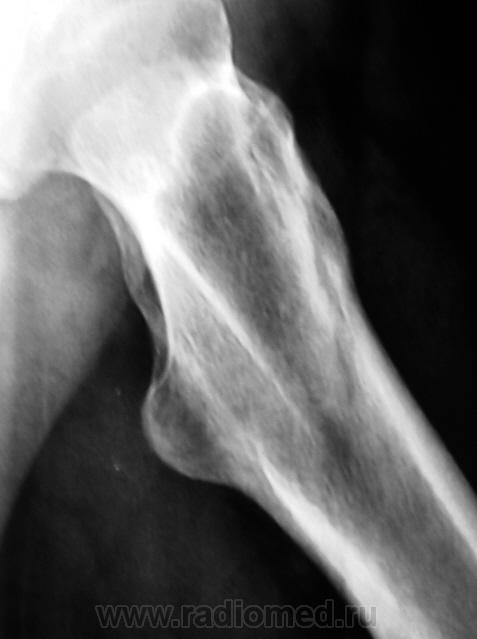

Травма 1 месяц тому. Пациент был направлен в рентгеновский кабинет для рентгенографии ребер и тазобедренного сустава. Был обнаружен перелом 2 - х ребер, но со стороны тазобедренного сустава нарушения целостности костной ткани и смещения костных отломков обнаружено не было.

Однако, пациент продолжал предъявлять жалобы на боли в области верхней трети бедра. Произведена рентгенография.

Линия перелома косая, начало -сразу за шейкой а на противоположный контур кости -выходит ниже основания большого вертела... Хорошо, что практически без смещения.

Уважаемые корифеи! Что-то я сомневаюсь в переломе. Уж больно широкая и прерывистая линия получается. И в механизм не укладывается - где разрыв, где растяжение? Кистозную перестройку в большом бугре и в краиних к нему границах усматриваю.

А ведь и вправду - линия широковата...и идет то она как раз по краю большого вертела...не есть ли это просто игра теней....?

Тазобедренные суставы очень часто преподносят сюрпризы. Одним из них является вколоченный перелом шейки бедренной кости. За перелом в данном случае говорит:

1. Нескругленный угол между головкой и шейкой. Природа не любит острых (в смысле "нескругленных") углов.

2,Ненормальное расположение головки относительно шейки.

Все это потому, что произошло небольшое угловое смещение головки (или, правильнее, шейки), угол открыт кверху и латерально.

Укладка практически идеальная, а головка, если внимательно присмотреться, не на месте. А невидимость линии уплотнения - это тоже один из сюрпризов шейки бедра. Хотя, искать ее надо на первых снимках, да и то не всегда увидишь. Через месяц искать нужно тонкую полоску разряжения.

Так и где же тогда такая полоска? То что имеем - это широкая, местами прерывистая полоса просветления по контуру большого вертела....как мне кажется (см.первые снимки), ведь срок уже после травмы немалый...